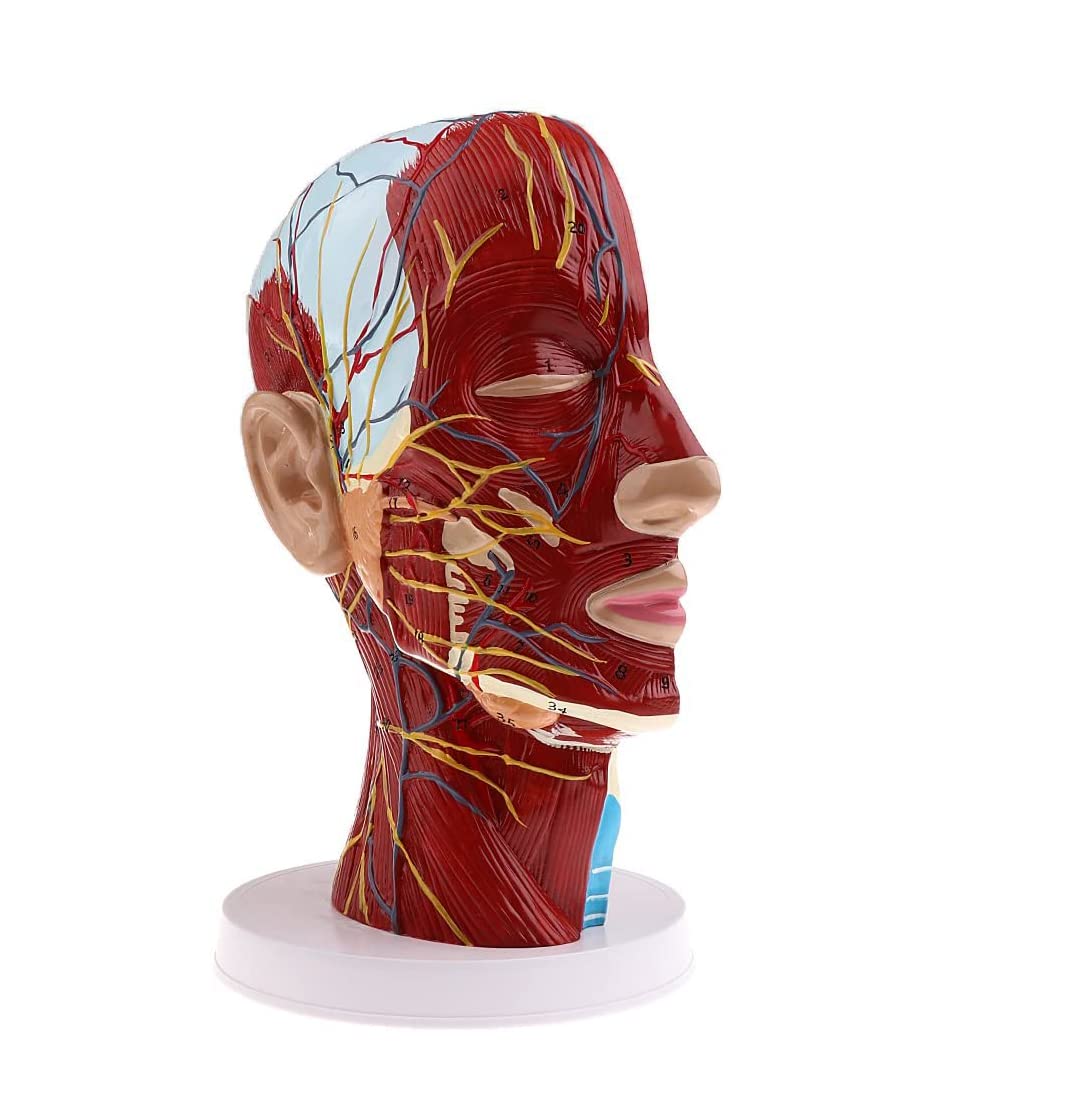

Description:A natural lifesize superficial neurovascular muscle modelMaterial: PVC, PC programmed advanced paintingHighly accurate 3D printing and spatial structureShows details of the human right head and neck and median sagittal plane, including exposed superficial muscles of face, superficial blood vessels, nerves, and parotids of face and scalp, the inner structure of the upper respiratory tract and the sagittal section of cervical spineSuitable for teaching, display, presentation and demonstration in hospital and aesthetic field.Specification:Size: 27 x 21 x 21.5 cm/ 10.6 x 8.3 x 8.5 inchPackage Includes:1 Piece brain model